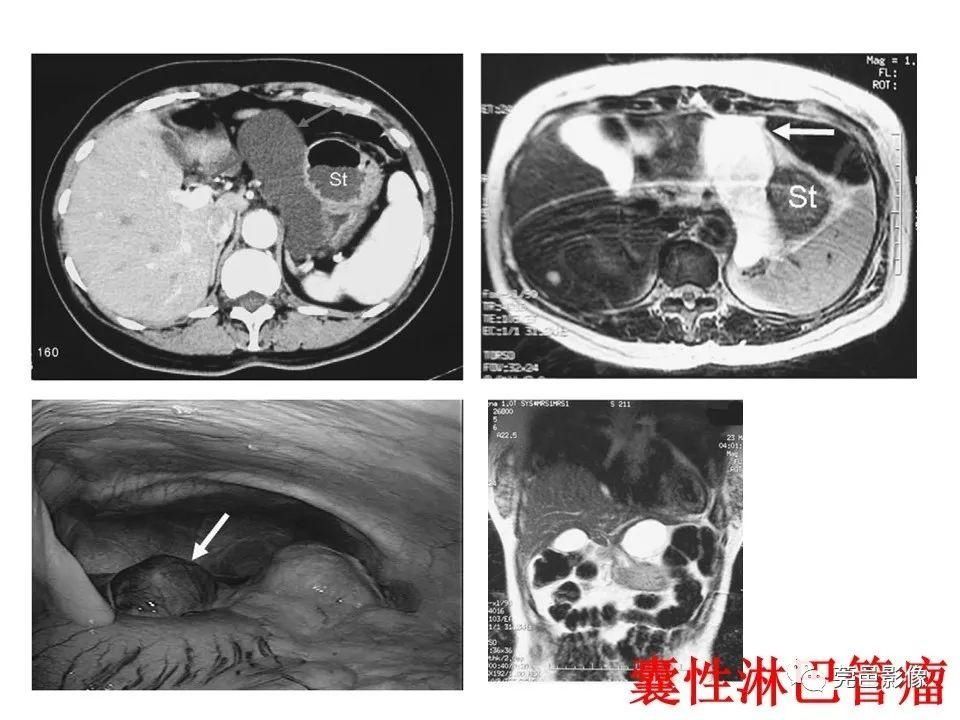

又称迷走胰腺或副胰。拥有独立的血液供应和神经支配;一种先天性畸形,机制尚不十分清楚。可能是胚胎时期胰腺始基与原肠粘连或穿透原肠壁,并随原肠纵向生长及旋转而被异常移植。或者由异常部位的内胚层细胞异向分化和化生而来;异位胰腺最常发生部位是十二指肠,其次是胃和空肠;症状的产生主要与异位胰腺的解剖位置和并发症有关,与病灶的功能状况和病变发展程度也有一定的关系;正常部位胰腺的任何疾病均可发生于异位胰腺,如胰腺炎、囊肿、腺瘤或腺癌等;消化道内镜为诊断的首选方法。